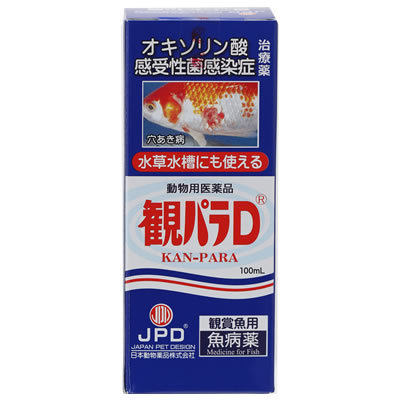

- 観パラD